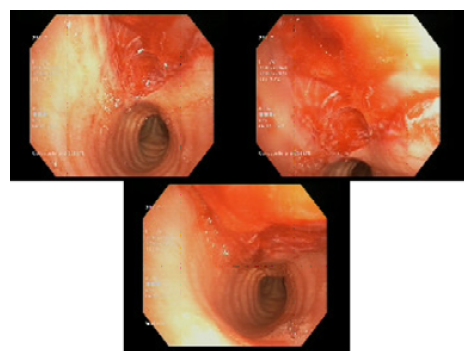

During her stay in the PACU, approximately 20 minutes after the end of surgery, the patient presented several episodes of hemoptysis accompanied by dyspnea and oxygen saturation of 95% which improved with supplemental oxygen at 2L through a nasal cannula. Pulmonary auscultation at that time was unremarkable and no subcutaneous emphysema was found in any location. The case was immediately discussed with the Pulmonology Department, which proceeded to perform a fibrobronchoscopy that showed an erosive, lacerated and bleeding injury of 1.5cm in length on the posterior wall of the trachea and 5cm from the vocal cords (Figure 1). However, due to the active bleeding, it was not possible to establish the depth of the lesion in the thickness of the tracheal wall.

After discharge, the patient was referred to the Thoracic Surgery Department and at her first follow-up, 10 days after the incident, it was found that she was asymptomatic and continued antibiotic treatment until 10 days had elapsed. During the second follow-up, 20 days after the tracheal laceration, a new fibrobronchoscopy was performed, which showed the tracheal mucosa had healed (Figure 2), so the Thoracic Surgery Department discharged her and indicated that she should be followed up by her primary care physician.